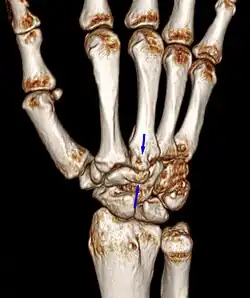

Carpal boss VR-3D-Reconstruction

Carpometacarpal boss is uncommon and there is not much scientific data. Its etiology has yet to be fully defined, but can be congenital in the form of an accessory ossicle (os styloideum) or may be acquired from trauma, repetitive use, or degenerative osteophytosis.[3] The condition usually begins to show in the 3rd or 4th decade.